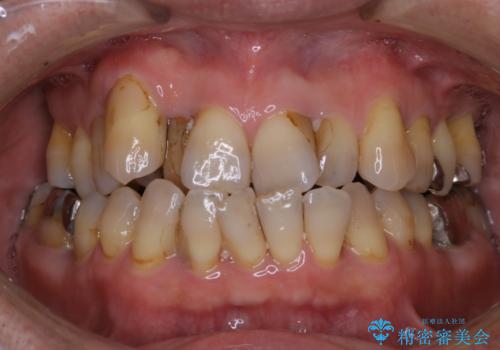

- これから、全体的な総合治療がスタートするため、着色や汚れをきれいにしてほしいとのことでした。PMTC60分コースを行いました。

また、治療が開始される前などにも、全体的にクリーニングを行いご自身本来の歯の色、状態を精密に確認することが大切です。